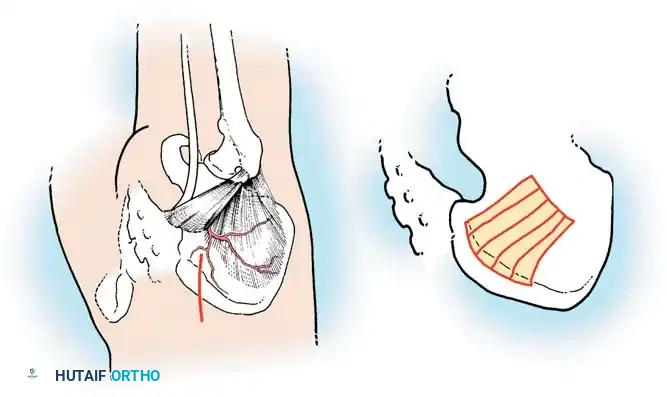

The Moe Technique (Lumbar Spine)

In the lumbar spine, the facet joints are oriented in a more sagittal plane, necessitating a modified approach.

Fig. 38-27: The Moe technique adapted for lumbar facet fusion, addressing the sagittal orientation of the joints.

- Utilize a small osteotome or a needle-nose rongeur to resect the adjoining joint surfaces.

- This creates a distinct rectangular defect within the sagittally oriented joint space.

- Pack this defect forcefully with cancellous bone graft.

- Proceed to decorticate the entire exposed posterior elements (laminae and transverse processes) using Cobb gouges, always directing force away from the spinal canal.

The Hall Technique

The Hall technique offers an alternative method for facet obliteration and grafting, particularly useful in rigid deformities.

Fig. 38-28: The Hall technique of facet fusion, involving sharp excision of the inferior facet and trough creation.

- Sharply amputate the inferior articular facet with a gouge and remove the bone fragment entirely. This exposes the cartilage of the superior facet.

- Remove the exposed cartilage completely with a sharp curet.

- Create a bleeding trough by removing the outer cortex of the superior facet.

- Impact cancellous bone grafts directly into this vascularized trough.

- Complete the procedure with global decortication of the posterior elements.